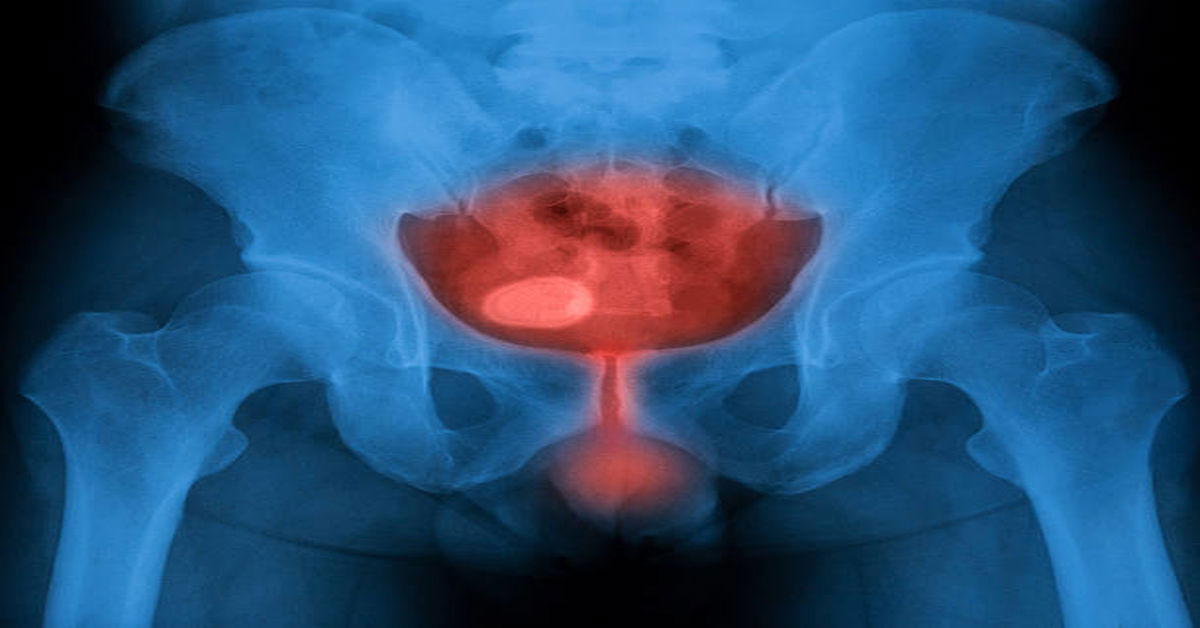

Воспаление мочевого пузыря

Это воспаление внутренней поверхности мочевого пузыря вследствие инфекции. Обычно это вызвано инфекциями мочевыводящих путей. Это состояние проявляется такими симптомами, как болезненное мочеиспускание, частое мочеиспускание, а также мутная или неприятный запах мочи. воспаление мочевого пузыря Если его не лечить, это может привести к более серьезным проблемам со здоровьем. Ранняя диагностика и лечение предотвращают распространение инфекции.